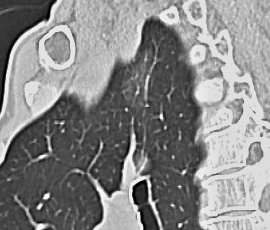

[肺がん] 手術:胸腔鏡下肺悪性腫瘍手術(区域切除)

CT画像